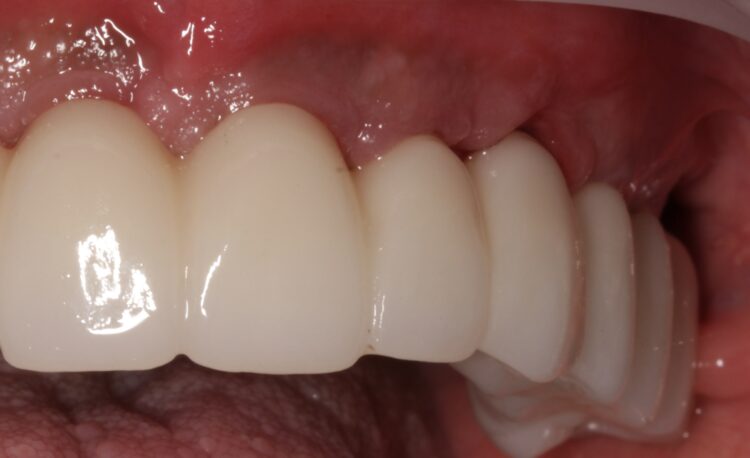

Based on the digital design and copying the approved provisional prosthesis, a zirconia overlay was milled. The overlaying zirconia superstructure was digitally designed to fit the metal substructure, accomplish a flawless finish line, avoid any undercuts and verify the path of insertion, thus facilitating the bonding procedures. The zirconia superstructure was bonded with the titanium substructure using a self-curing luting composite. The final polished screw-retained prosthesis was delivered and torqued to 30Ncm and the radiographic assessment was executed.

After the follow up appointments at one and four weeks, the patient was scheduled for periodic maintenance every three months. The retrievability of the final screw-retained zirconia-titanium supported prosthesis allowed management of the interface over time. At the one-year review, further growth and maturation of the soft tissue as well as the health of the keratinised peri-implant tissues were evident, without signs of bleeding on probing.

Particularly in FP1 cases where a correct emergence profile has to be formed through the implant-supported immediate temporary prosthesis, a digital treatment plan and guided surgery offer a comprehensive workflow to achieve predictable high-end prosthetic results that mimic the natural dentition.

The translucent zirconia supported by titanium framework fulfils the aesthetic and mechanical requirements of an FP1 full arch prosthesis, while minimising the risk of fracture by providing a rigid yet passive joint to support the implants.[vi] The zirconia and titanium transmucosal surface characteristics (otherwise known as biocompatibility) create a highly polished interface for high cell adhesion and optimised gingival architecture.